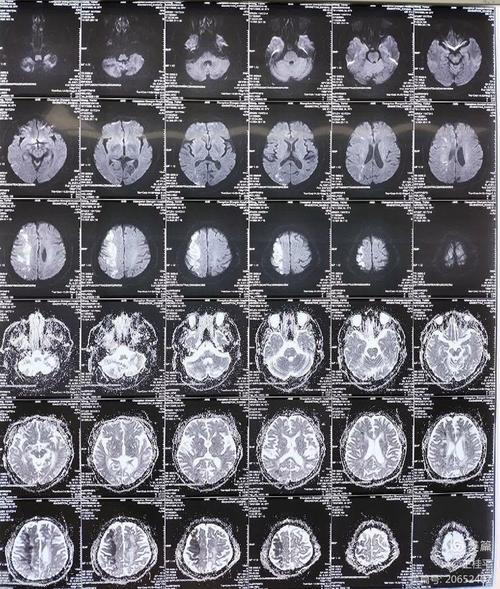

头颅MRI(磁共振成像)

- 金标准:是目前诊断脑梗最敏感、最准确的检查方法。

- DWI序列(弥散加权成像):可以在发病后几分钟到1小时内就发现缺血病灶,极大地提前了诊断时间,为溶栓和取栓赢得了宝贵的时间。

- 对早期和微小梗塞灶更敏感:能发现CT无法显示的小梗塞。